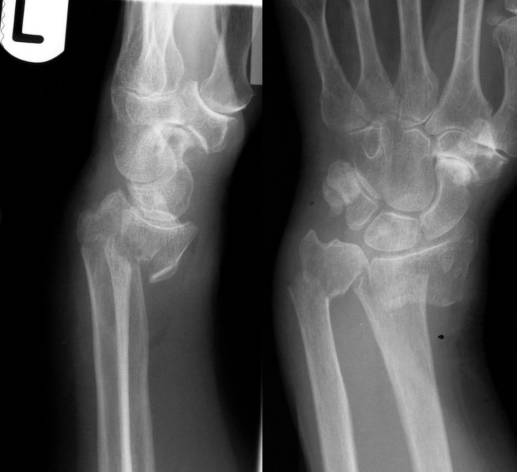

Barton骨折

桡骨远端关节内骨折,伴桡腕关节脱位。